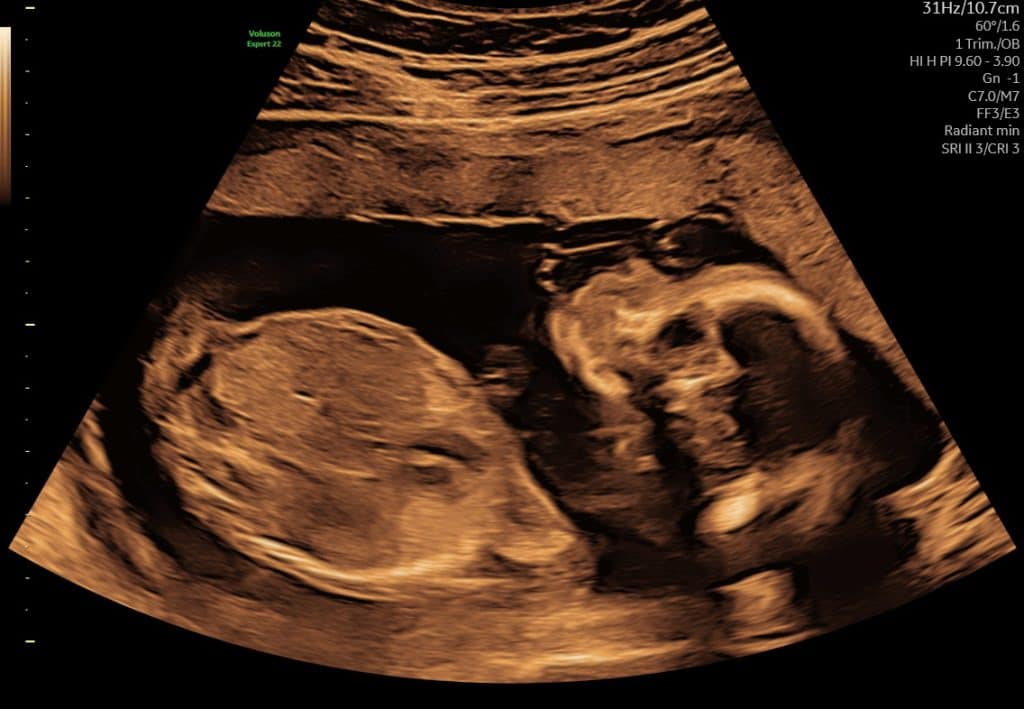

Ultralyd uge 12 – mere detaljeret anatomi

Omkring uge 12 er fosteret tydeligt udviklet. Man kan se:

Nakkefold (ved relevant scanning)ode, at mange vælger scanning i forbindelse med risikovurdering, fx nakkefoldsscanning, hvis man ønsker det. Billedkvaliteten er ofte god, men fosteret er stadig relativt lille.

Arme og ben

Bevægelser

Ultralydsscanning uge 11

Ultralydsscanning uge 10

Eksempel på ultralyd i uge 11–13. Fosterets bevægelser kan ofte ses tydeligt.